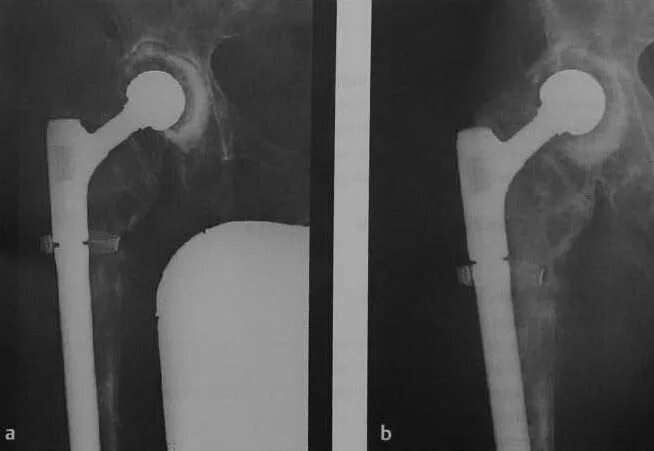

Можно ли эндопротезом делать мрт